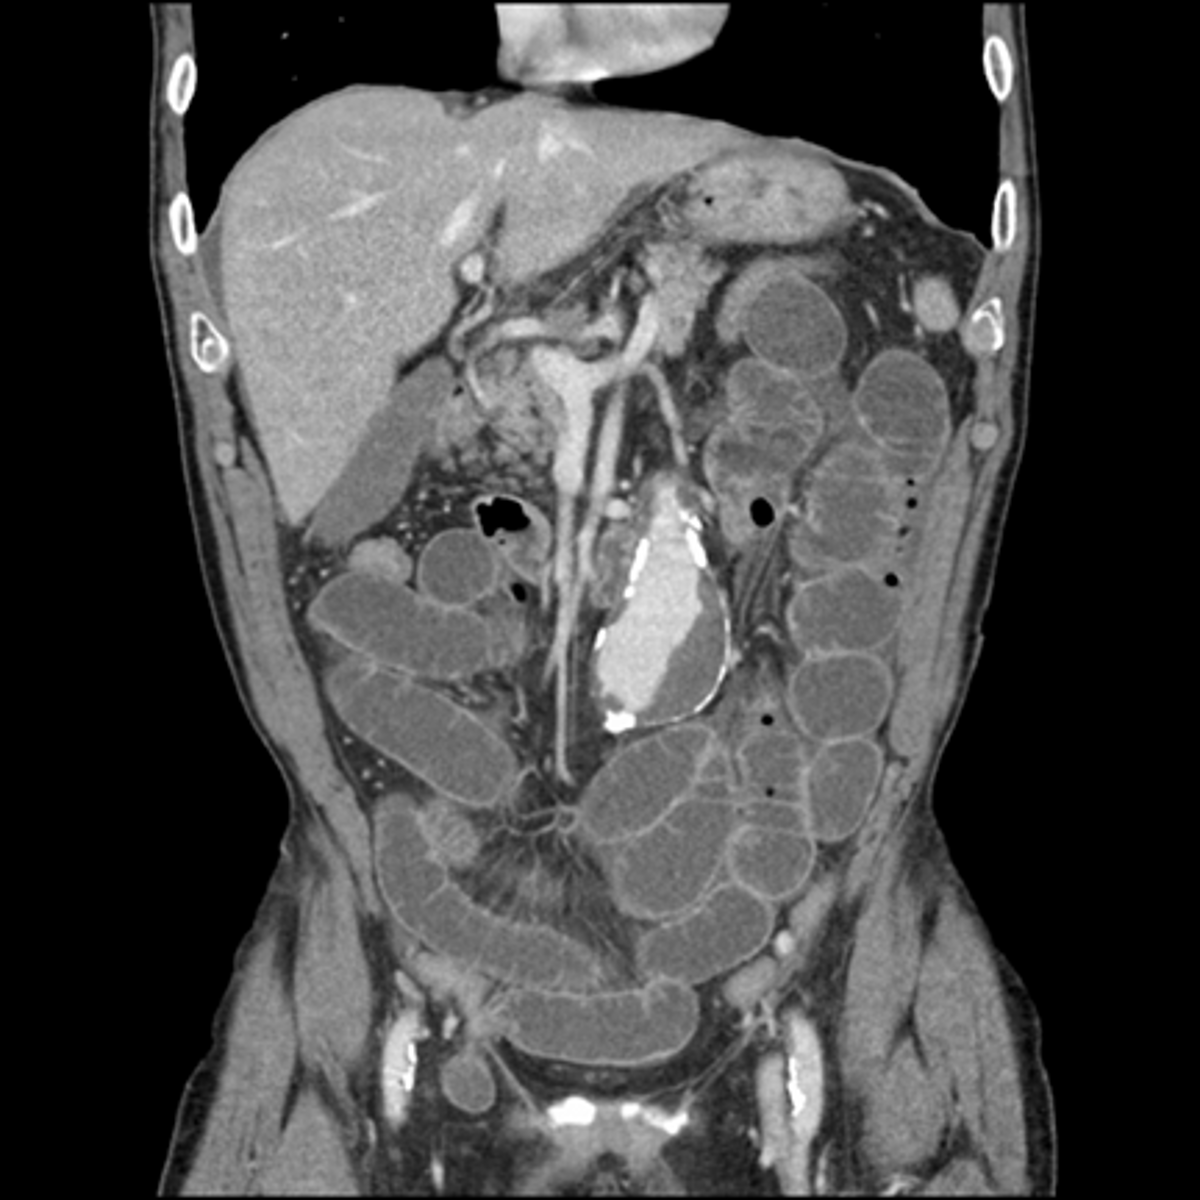

Partial SBO.

SOLID WHITE ARROWS: dilated and contrast containing loop of small bowel

DOTTED WHITE ARROWS: air in collapsed colon

Coronal-reformatted CT with oral contrast shows dilated and contrast-containing loops of small bowel. Although there is still air in the collapsed colon, the disproportionate dilatation of small bowel identifies this as a small bowel obstruction.